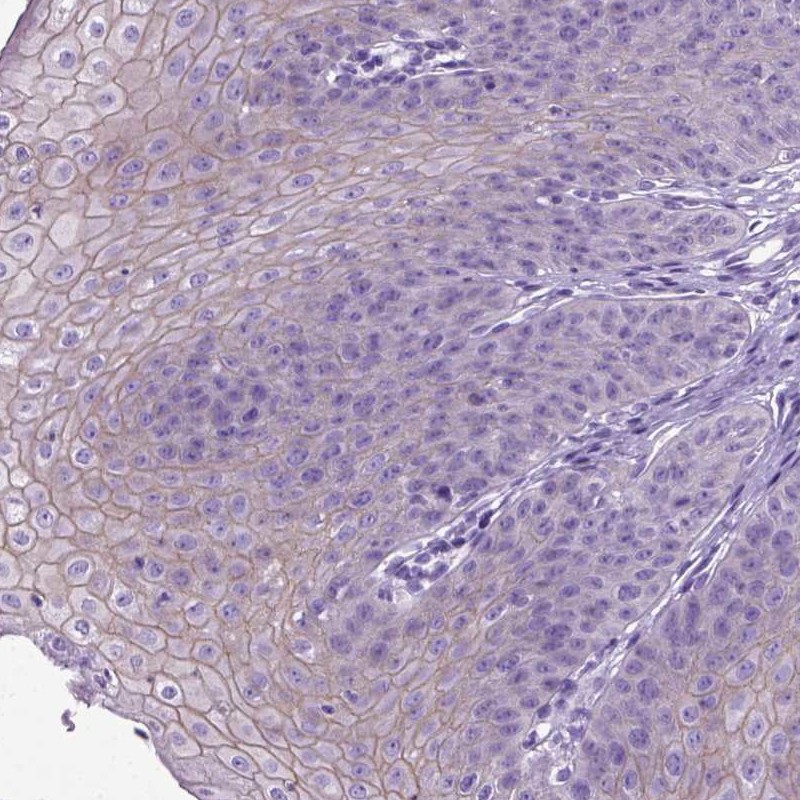

Immunohistochemistry analysis in human esophagus and skeletal muscle tissues using Anti-PPL antibody. Corresponding PPL RNA-seq data are presented for the same tissues.